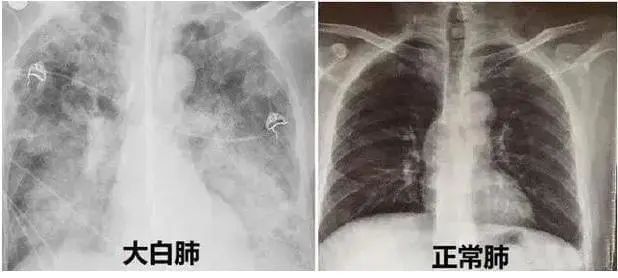

近期,多地醫(yī)生發(fā)現(xiàn)患者出現(xiàn)肺炎或白肺癥狀,引發(fā)關(guān)注。那么什么是白肺呢?其實白肺是肺部影像學(xué)表現(xiàn)的一個口語化描述。當(dāng)出現(xiàn)炎癥和感染,肺泡被滲出液等填充,在影像學(xué)上的表現(xiàn)就是出現(xiàn)白色區(qū)域。并不是只要肺部出現(xiàn)了炎癥就都叫白肺,一般來講肺部炎癥較重、滲出液較多,白色的影像區(qū)域面積達到70%?80%時,在臨床上把它稱為白肺。通過“啄醫(yī)生”可以準確地識別新冠肺炎的典型白肺影像,以下選取幾例最新病例加以說明。

案例一,61歲,女性,確診病例

胸片顯示整個雙肺已經(jīng)白化

影像所見:有慢性阻塞性肺疾病病史。2周前受涼后出現(xiàn)發(fā)熱,伴咳嗽、咳痰。入院后給予吸氧,5天后出現(xiàn)口唇紫紺 ,改為BIPAP呼吸機輔助通氣。12月14日和12月18日,兩肺病灶自肺野外周、下后部向中心和上部迅速擴展,表現(xiàn)為“白肺”。